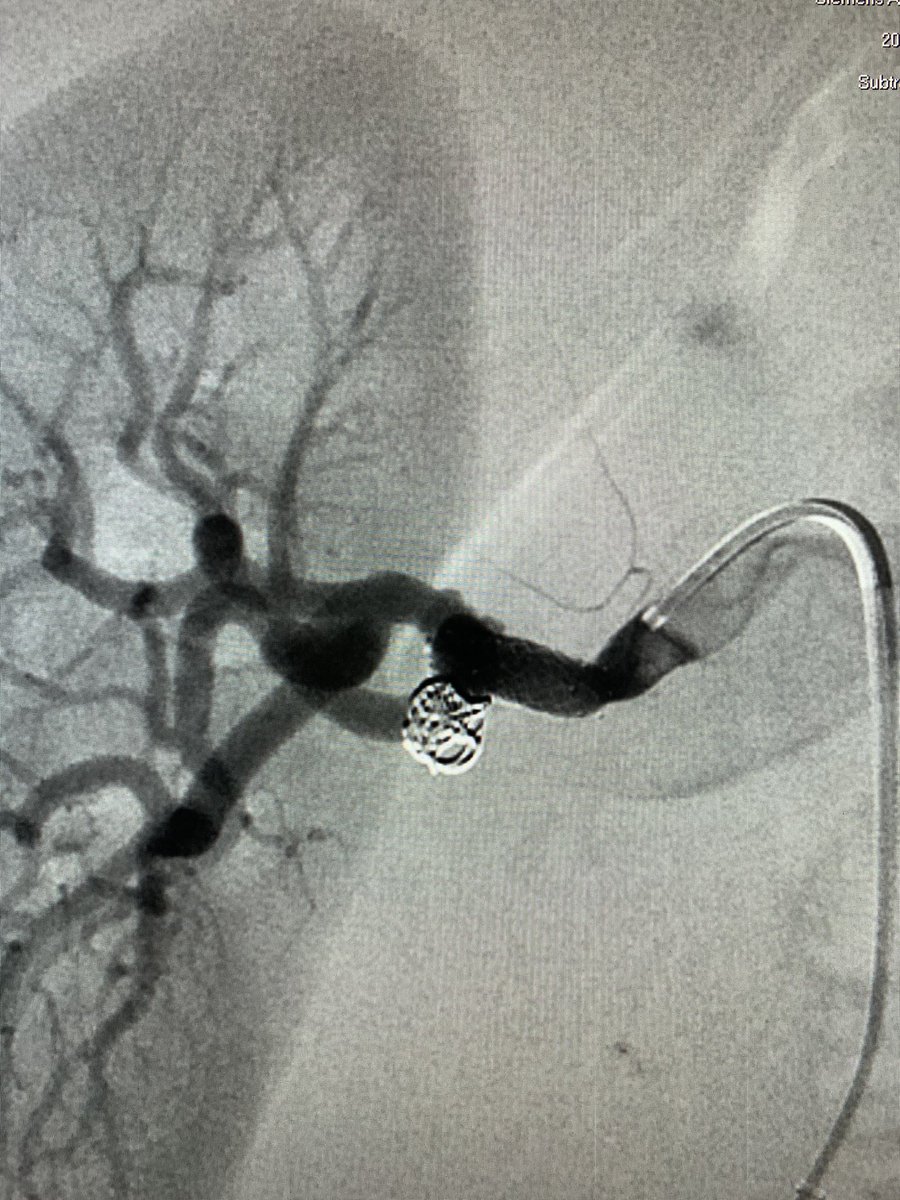

WEB can be used in various anatomical locations. We treated a wide-necked renal artery aneurysm with a WEB by ”corking” the neck. Immediate contrast stagnation!